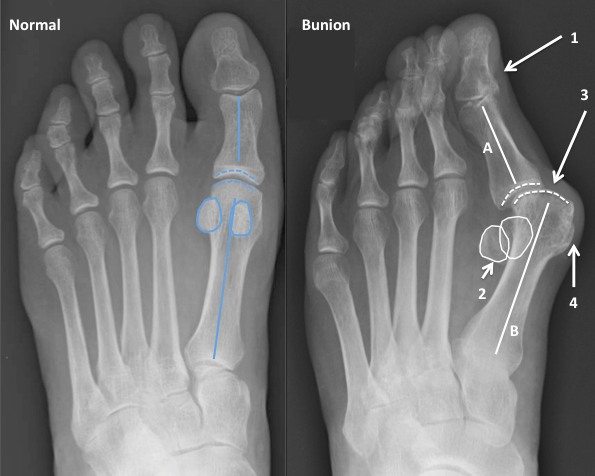

Рентген после операции Hallux valgus

Раздел: Фокус на знании